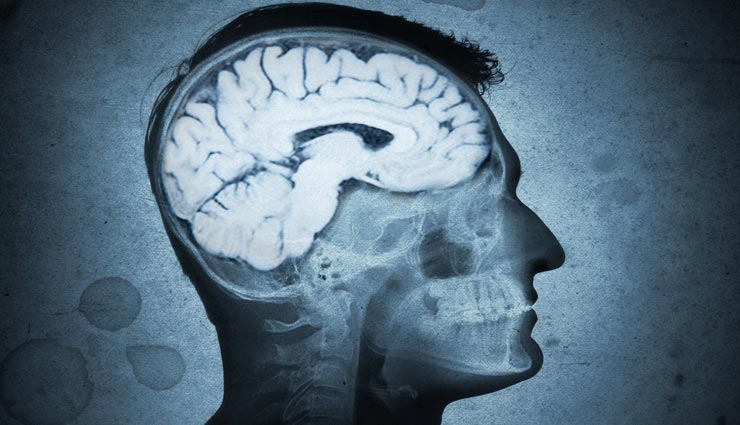

चूंकि झांग का सिर दर्द लंबा नहीं रहता था, इसलिए वो हर रोज दवाई नहीं खाते थे। लेकिन साल 2015 में उनकी समस्या और ज्यादा तब बढ़ गई, जब गांव में आग लगी थी। इसके बाद से उन्हें हर महीने तेज सिर दर्द होने लगा और चक्कर खाकर बेहोश होने लगे। जब झांग की परेशानी बढ़ गई तो वो एक बार फिर डॉक्टर के पास पहुंचे, लेकिन उनका साफ कहना था कि ये परेशानी मिर्गी की वजह से ही है। हालांकि झांग को संतुष्टि नहीं मिली और वो दूसरे अस्पताल में पहुंचे, जहां उनका एमआरआई स्कैन किया गया। तब जाकर सिर दर्द की असली और चौंकाने वाली वजह पता चली।

दरअसल, झांग के दिमाग में एक 10 सेंटीमीटर लंबा परजीवी था, जिसे सर्जरी के द्वारा निकाल दिया गया। इसमें सबसे ज्यादा हैरानी की बात तो ये थी कि वो परजीवी 30 साल से जिंदा था। यह देखकर डॉक्टर भी हैरान थे। झांग के दिमाग का ऑपरेशन करने वाले डॉक्टर यान जुईकियांग के मुताबिक, नदी का पानी पीने या आधा पका झींगा खाने से ऐसे इंफेक्शन हो सकते हैं, जैसा झांग को हुआ था। चूंकि झांग के गांव में लोग नदी का ही पानी पीते हैं और झींगा खूब खाते हैं, इसलिए डॉक्टर यान का मानना है कि झांग के दिमाग में इसी वजह से ये सिर दर्द की परेशानी हुई होगी।